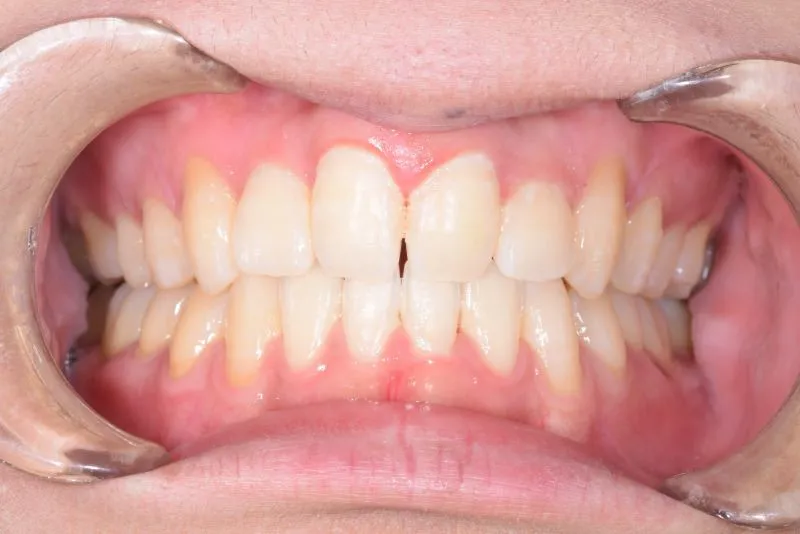

• 治療終了後

治療終了後

治療回数42回、3年1ヶ月の治療期間で矯正治療を終了しました。

主訴が改善され、ご満足頂きました。

正中のすき間については保定期間にも調整しています。